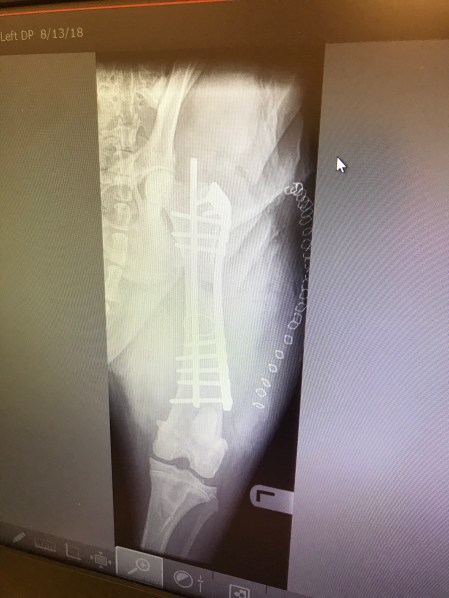

I’m not worried. Yet. He was 100% sound walk, trot, canter and jumping when he was shod up front. I had his PPE and he trotted off sound for every limb and his joints all looked good on xray. Trainer gave me two lessons on him and watched him move very well and even commented on how nice his trot was. Then he ripped his hoof off and went lame. With no other explainable reason for acute onset lameness, I’m blaming his bad feet.